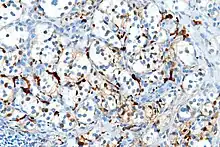

With immunohistochemistry, the chief cells located in the cell balls are positive for chromogranin, synaptophysin, neuron specific enolase, serotonin, neurofilament and Neural cell adhesion molecule; they are S-100 protein negative. The sustentacular cells are S-100 positive and focally positive for glial fibrillary acidic protein. By histochemistry, the paraganglioma cells are argyrophilic, periodic acid Schiff negative, mucicarmine negative, and argentaffin negative.

- S100 immunostain highlighting the sustentacular cells in a paraganglioma